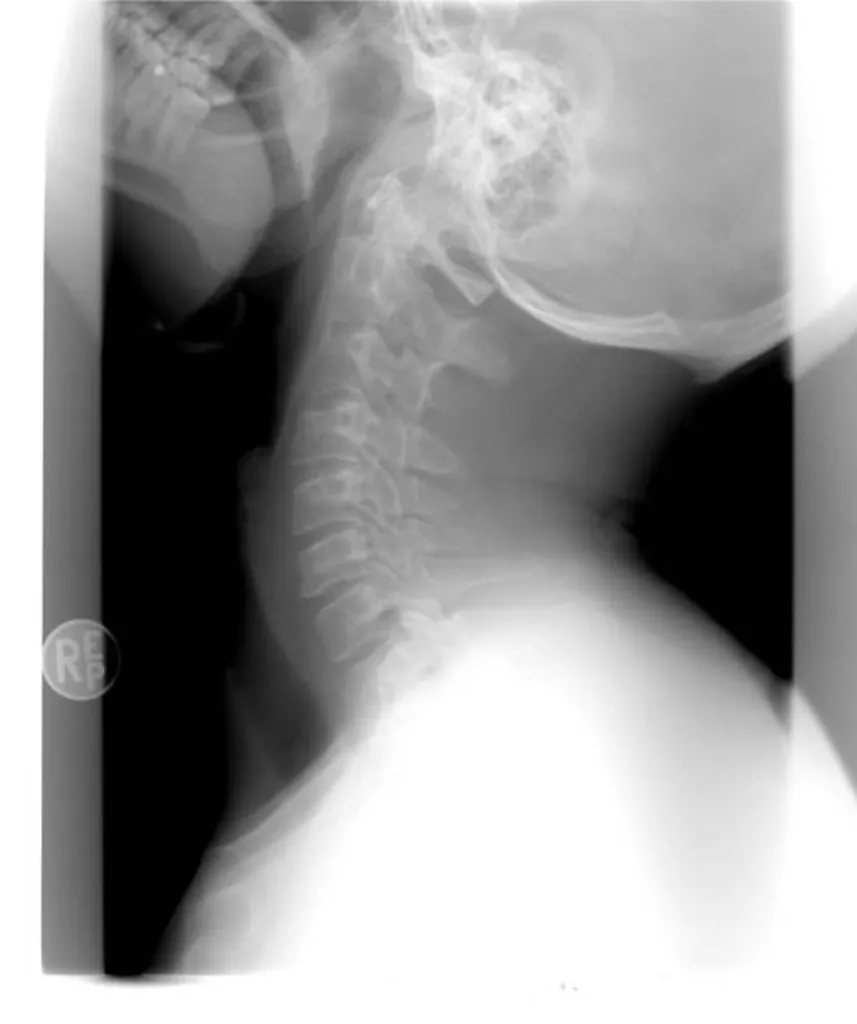

Indemnisation entorse cervicale suite à accident de la route Toulon et Var 83

Avocat pour l'indemnisation de dommage corporel du conducteur victime d'accident de la route ayant subi un "coup du lapin" ou entorse cervicale lors d'un choc arrière à Marseille

Le conducteur victime d'un accident de la route ayant subi un  "coup du lapin" ou entorse cervicale lors d'un choc arrière à Marseille a droit à l'indemnisation de son dommage corporel sur le fondement de la loi du 5 juillet 1985. L'assistance par un avocat est toutefois nécessaire pour être bi...